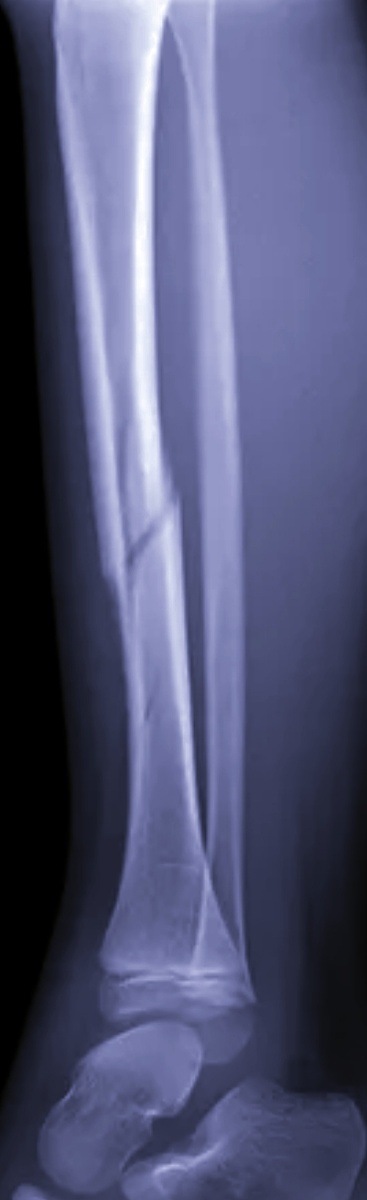

Мужчина , 33 года , на госпитализацию, гипс на ноге, сам на сидячей каталке Назначили голень и легкие.

-А я был у вас уже , четыре дня назад,-весело пояснил чуть помятого вида пациент, видно, что праздники не прошли мимо него.

–Ногу-то где сломали?

–Дома и сломал, со ступени соскользнула.

-Вытягивайте ногу , вот сюда укладывайте.

–Так мне делали снимки, я вот вам про что.

–И что? Четыре дня прошло, мало ли , что там еще сместилось.

–Ааа, а я думал, что те пригодятся.

Не видела я предыдущие снимки , но подозреваю , что пациент явно не лежал в кроватке)

У нас много таких, которые уходят домой после репозиции и гипса, а потом приходят на госпитализацию, допраздновав-таки праздники, кто на следующий день , а когда и через неделю.